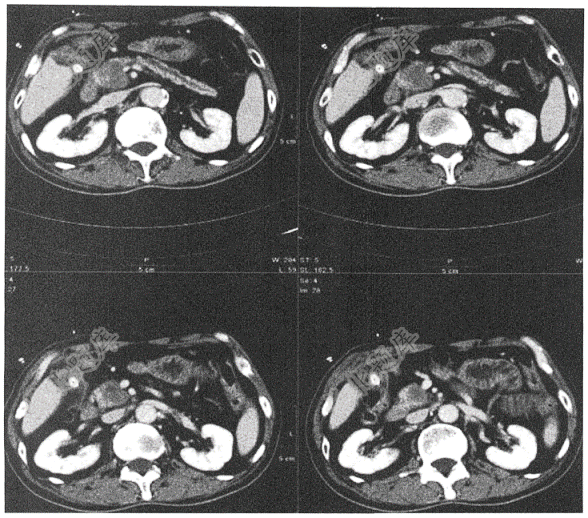

- 单项选择题男性,48岁,腹痛( )

D、急性胰腺炎

E、慢性胰腺炎